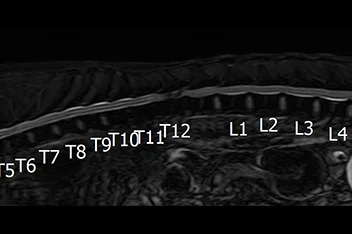

• 흉요추 디스크 MRI

• 흉요추 디스크